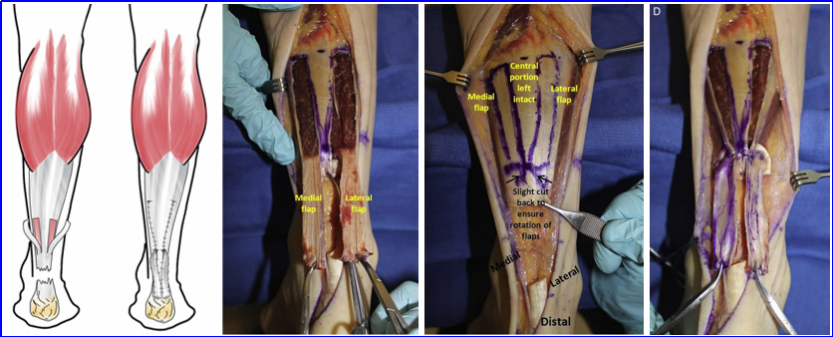

V-Y延长可闭合<5 cm缺损,术中保持腱膜完整以保证血供;

手术方法为:在近端腱膜中央做倒 “V” 形切口,顶点位于近端。“V” 形切口的边长应为间隙长度的1.5 倍,以便将近端腱膜以“Y” 形缝合闭合。切口两侧需全程切开腱膜及其深面的肌肉组织,直至肌腱瓣两侧。

图 10. (A)在近端腱膜做倒 “V” 形切口,以闭合慢性跟腱断裂的断端间隙。(B)肌腱推进后间隙闭合,“V” 形切口缝合转为 “Y” 形。

V-Y 成形术是跟腱再损伤中最常用的术式,但单纯 V-Y 推进术存在不足;通常需要联合其他手术技术才能获得足够的延长效果。

腓肠肌V-Y推进术+腓肠肌筋膜翻转术:>5 cm联合腓肠肌筋膜翻转术,但切口长达12 cm,皮肤缘坏死率8%,术前需评估吸烟、糖耐量等血管风险并设计波浪切口减张。